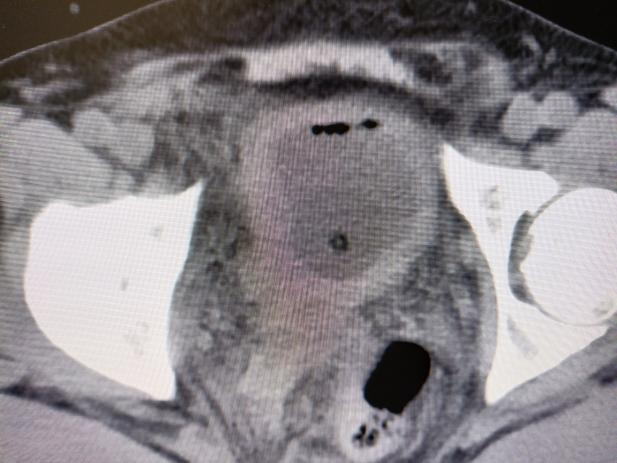

经泌尿外科团队讨论后,决定为患者施行腹腔镜下膀胱巨大憩室切除术,手术顺利。术后拔除尿管后,罗大叔排尿通畅、症状消失,非常满意。出院时罗大叔高兴的说:“我以为要开大刀,没想到几个小孔就解决了,你们的技术真的好!” 术前影像 术后影像 切下来的膀胱憩室 微创小孔 科普知识 什么是膀胱憩室?它有什么危害吗? 膀胱憩室主要是由于患者膀胱肌肉先天性的薄弱,或者是由于尿路梗阻导致的膀胱内压的升高,最终在膀胱壁表面形成了一个膀胱黏膜经膀胱壁肌层向外膨出的囊袋,就好像是多了一个膀胱一样。如果憩室较小,可无明显症状。但如果憩室较大,则会出现排尿困难、尿频、尿急、尿痛、血尿以及两段排尿等相关症状,严重时可出现严重的并发症。 并发症: 1.便秘-膀胱憩室压迫到了患者的直肠,从而导致患者出现便秘。 2.难产-巨大的膀胱憩室压迫到子宫,导致女性患者难产。 3.憩室感染、憩室结石-患者可出现尿频、尿急、尿痛等尿路感染的症状,严重者甚至并发憩室结石。 4.尿路梗阻-憩室增大可以压迫输尿管使之产生位移,从而出现梗阻。 5.肾功能不全或者肾衰竭-当患者的憩室增大导致出现尿路梗阻,如梗阻进一步发展,使得肾小囊内压力增高造成肾小球率过滤的降低,尿量减少,肌酐、尿素氮排出受阻,严重者可以出现肾功能不全或者肾功能衰竭。 6.尿潴留-膀胱憩室压迫膀胱出口,出现尿潴留。 7.癌变-膀胱憩室易合并有癌变,患者可表现为无痛性肉眼血尿。 合江县人民医院泌尿外科近年来大力发展腹腔镜技术,目前能开展的腹腔镜技术有:腹腔镜下肾癌根治术、腹腔镜肾盂癌根治术,腹腔镜无功能肾切除术,腹腔镜肾上腺肿瘤切除术,腹腔镜肾囊肿去顶减压术、腹腔镜前列腺癌根治术、腹腔镜膀胱全切术、腹腔镜精索静脉曲张高位结扎术,腹腔镜下输尿管切开取石术,腹腔镜输尿管狭窄切除吻合术,腹腔镜输尿管膀胱再植术等。 泌尿外科专科门诊:门诊综合楼二楼212诊室。 特需专家门诊:每周四上午,门诊综合楼一楼113诊室。 泌尿外科住院部:住院综合大楼五楼。 咨询电话:0830-5266595